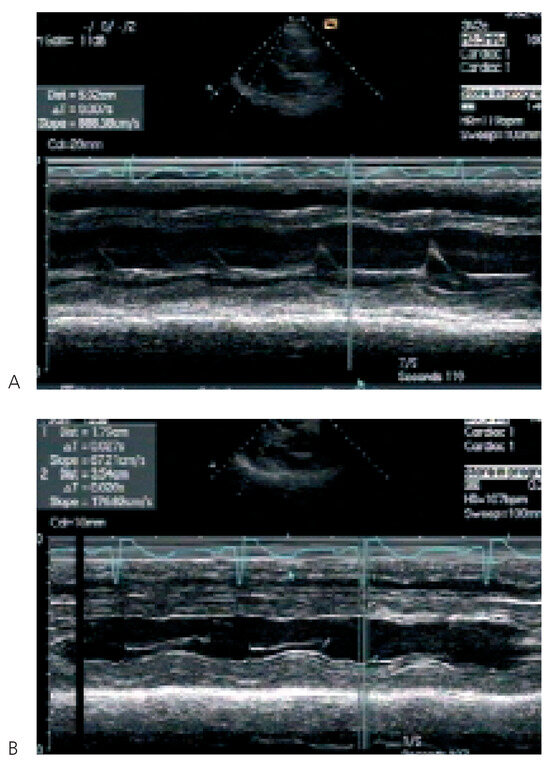

Update on Left Ventricular Hypertrophy

by Christina Attenhofer Jost

Detection and evaluation of left ventricular hypertrophy of unknown etiology by echocardiography is important in every cardiology practice. Causes of left ventricular hypertrophy include sarcomeric protein disorders (classical hypertrophic cardiomyopathy), metabolic disease (glycogen storage disease including LAMP2 deficiency, PRKAG2 mutations, Fabry disease), syndromic [...] Read more.

Detection and evaluation of left ventricular hypertrophy of unknown etiology by echocardiography is important in every cardiology practice. Causes of left ventricular hypertrophy include sarcomeric protein disorders (classical hypertrophic cardiomyopathy), metabolic disease (glycogen storage disease including LAMP2 deficiency, PRKAG2 mutations, Fabry disease), syndromic hypertrophic cardiomyopathy (Noonan’s syndrome, LEOPARD syndrome, etc.) and miscellaneous causes including systemic hypertension, amyloidosis, athlete’s heart and pheochromocytoma. Although there are several echocardiographic changes quite typical for some of the disorders, most changes are not 100% specific. ECG findings and symptoms provide important additional information. Genetic testing is increasingly important. Nowadays, a combination of ECG findings, symptoms, family history, genetic testing and findings of echocardiography provide the best means for differentiation of left ventricular hypertrophy. Full article

Figure 1